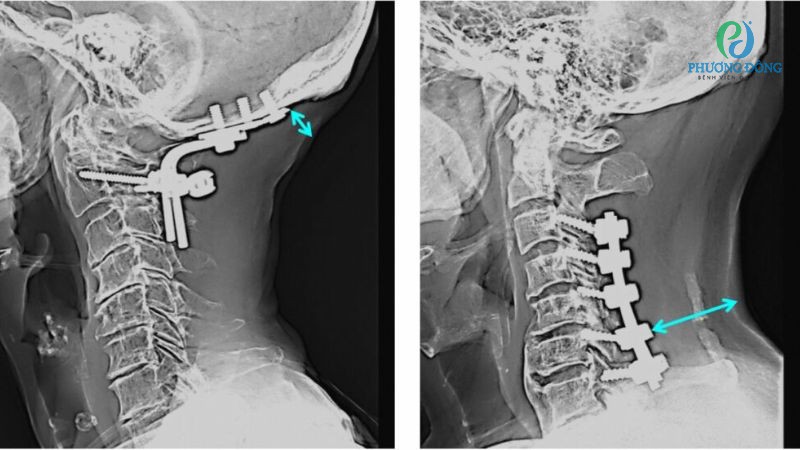

- Phẫu thuật chỉ được xem xét thực hiện khi hai phương pháp nêu trên không đạt hiệu quả, tình trạng thoái hóa đốt sống cổ diễn tiến nghiêm trọng.

Điều trị tình trạng thoái hóa cột sống cổ chèn dây thần kinh